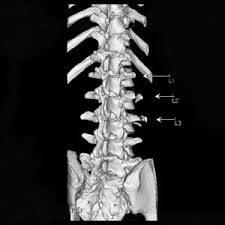

A transverse process fracture is a break in 1 or more transverse process. There is one on both sides of every vertebra in the… a transverse process fracture is quite a rare injury. Transverse process fractures are common sequelae of trauma, although they are considered a minor and stable lumbar spine fracture. In 78% of transverse process fractures, ct scanning showed that the fracture extended into the transverse foramen. A transverse process fracture is a break in 1 or more transverse process.

A transverse process fracture at the level of l5 is a surrogate marker of vertical instability of the pelvic fracture due to the attachment of the iliolumbar ligaments. Possible causes, signs and symptoms, standard treatment options and means of care and support. Transverse processes are used as lever arms by the deep spinal muscles to maintain posture and to induce rotation and lateral bending. It may occur as an avulsion fracture due to strong contracture of the muscles. Although the fracture is not associated with spinal cord damage and neurological deficits, the extreme force of the injury can cause visceral injuries and internal hemorrhage. The presence of other injuries might also be assessed due to the level of force needed to break the transverse process. In 78% of transverse process fractures, ct scanning showed that the fracture extended into the transverse foramen. Transverse process fractures caused by stress are likely under detected since even an acute transverse process fracture requires a high index of suspicion to be correctly identified(4,7). Here is an example of a patient with a benign looking transverse process fracture with an associated significant injury to the back. Transverse process fracture you have fractured a transverse process. Thoracic transverse process fractures (ttpfs) are injuries that go unnoticed during traditional autopsies, as demonstrated by a lack of medicolegal publications regarding ttpfs. We retrospectively reviewed the reports of lumbar spine and abdominopelvic ct scans from 2017 and 2018 to classify the types of spine fractures, their mechanism of injury, treatment and. Up to 60% of lumbar transverse process fractures identified on ct will be missed on plain radiographs.

However, postmortem computed tomography (pmct) has made detection of this type of injury easy. There are two transverse processes that extend off each vertebra in the details: What is a transverse process fracture? It may occur as an avulsion fracture due to strong contracture of the muscles. It occurs as a result of sudden and extreme trauma. If ct confirms isolated injury lateral flexion/extension views are indicated to rule out dynamic instability. Vertebral angiography, performed in eight patients with fractures involving the transverse foramen, showed dissection or occlusion of the vertebral artery in seven (88%) instances. This part extends out from the side of the main body of the bone (called the vertebral body). A transverse process fracture at the level of l5 is a surrogate marker of vertical instability of the pelvic fracture due to the attachment of the iliolumbar ligaments. We retrospectively reviewed the reports of lumbar spine and abdominopelvic ct scans from 2017 and 2018 to classify the types of spine fractures, their mechanism of injury, treatment and. Up to 60% of lumbar transverse process fractures identified on ct will be missed on plain radiographs. In 78% of transverse process fractures, ct scanning showed that the fracture extended into the transverse foramen. Transverse process fractures identified on helical computed tomography (ct) scans without the presence of any other fracture or.